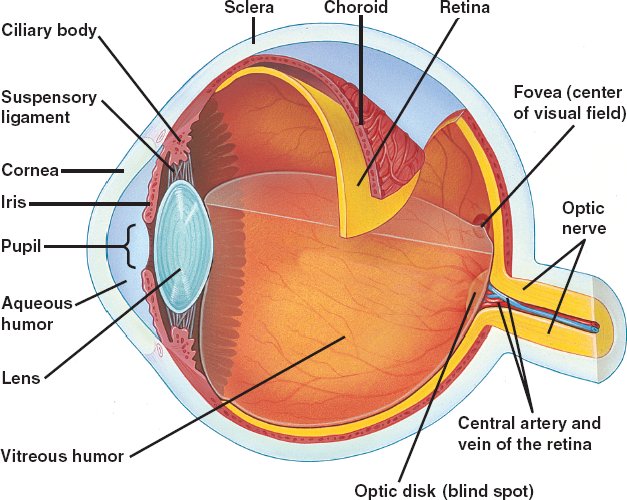

49_18VertEyeStructure

49_18VertEyeStructure_L

eye.html

vision.html